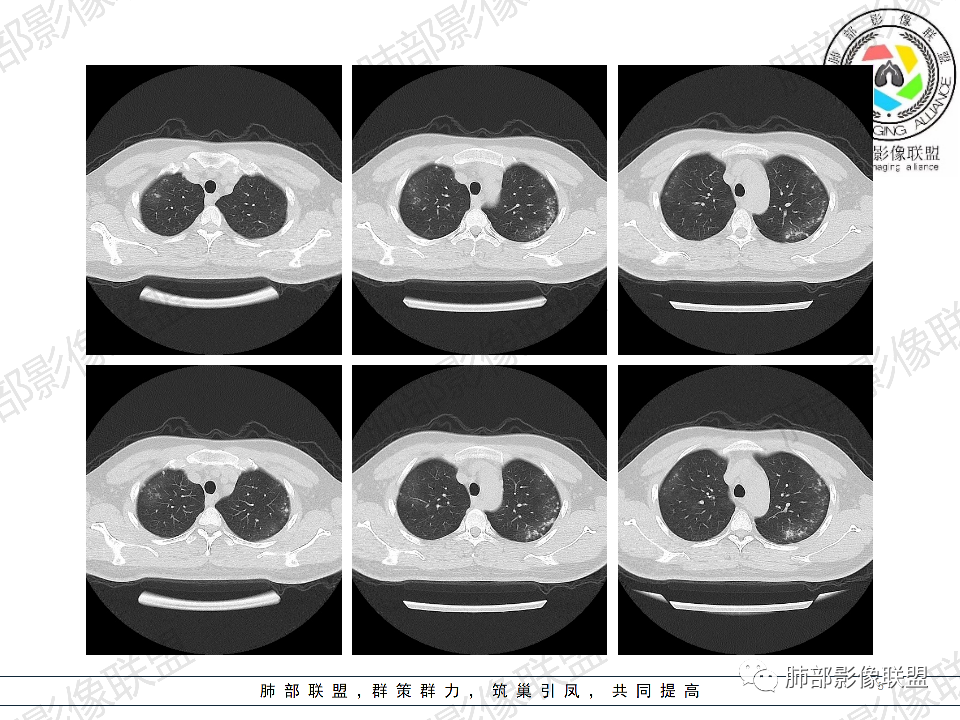

年轻男性,有HIV病史,免疫力缺陷病史,CD4明显减低,左肺胸膜下多发大小不等结节影,部分侧向融合,平行于胸膜,周围伴有模糊的GGO,部分结节与血管相连,血管束增粗,考虑隐球菌,建议查隐球菌荚膜实验,脑脊液隐球菌荚膜,鉴别:CMV(局限性比较少见)

年轻人,男性,HIV阳性,双肺多发斑片状,结节状阴影,以胸膜下分布为主,病灶与支气管血管束垂直生长,周围可见磨玻璃影,考虑肉芽肿病变,隐球菌感染可能性大,鉴别GPA,胞子菌肺炎。

双肺胸膜下多发大小不等结节伴晕征,部分似有融合

左肺多发大小不等结节影,部分融合,胸膜下分布为主,平行于胸膜,周围伴有磨玻璃晕,考虑隐球菌,鉴别:PJP

年轻男性,HIV阳性,胸闷喘憋,双肺胸膜下多发斑片结节影,周围伴晕,部分融合,白细胞低,CD4明显减低,考虑机会性感染性病变,隐球>PCP>结核

5、分布:病灶分布多位于胸膜下,可紧贴胸膜,也可与胸膜邻近,病灶长轴与胸膜平行。(划重点,分布特点非常重要)

10、“葫芦兄弟”:邻近胸膜多发结节,形态密度类似,可簇状分布,较少多形性,没有新旧不等。